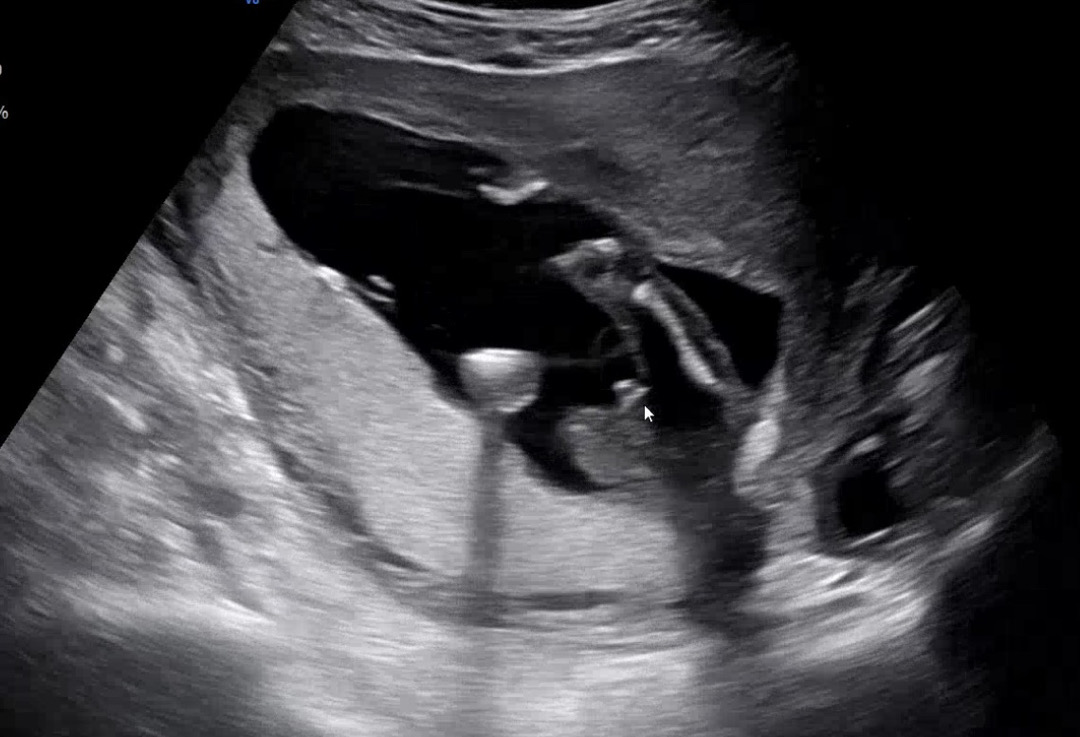

15주차 성별 봐주세요!

아들이라고 말씀 해주시긴 했는데, 바뀔 가능성은 없겠죠????! ㅎㅎㅎ

아들같아용 ㅠㅠㅠ20주 정밀초음파 때 다시 봐달라고 해보세요 !! 그 때는 거의 확실하더라구요